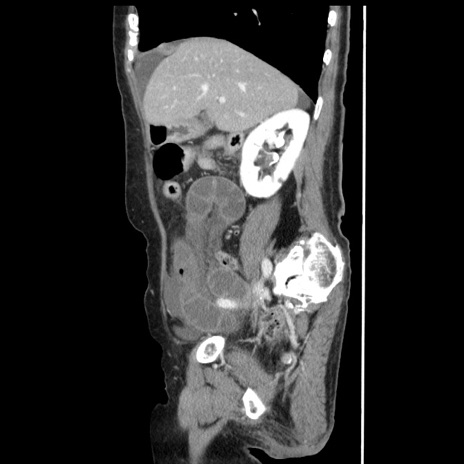

症例1(矢状断像)

【症例】80歳代女性

【主訴】腹痛

【現病歴】8時間前から腹痛あり来院。

【既往歴】糖尿病、脂質異常症、子宮体癌にて子宮全摘術

【身体所見】意識清明・会話良好だが腹痛で苦悶様、全腹部にわたって反跳痛と圧痛あり

【データ】WBC 13600、CRP 0.14、LDH 224、CK 90